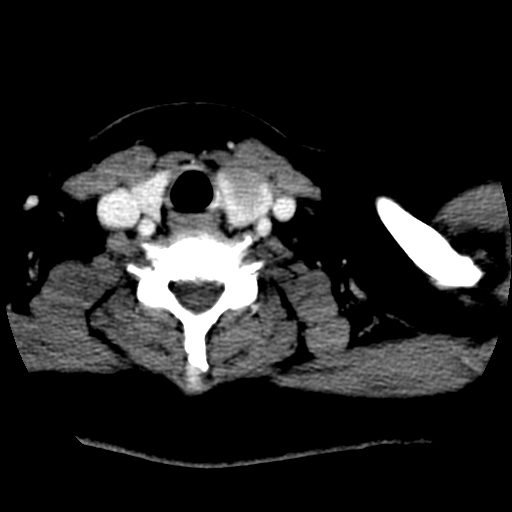

标题: CT25491:女,55岁,发现左侧甲状腺肿块一个月。 [打印本页]

标题: CT25491:女,55岁,发现左侧甲状腺肿块一个月。

女,55岁,发现左侧甲状腺肿块一个月,彩超示:甲状腺多发结节伴左叶结节液化。

左右叶都有,峡部也受累,有钙化,考虑结甲可能性大。

考虑右叶结节性甲状腺肿,伴左叶钙化。主要(1)密度均匀,边境清。(2)病灶与血管界限清。